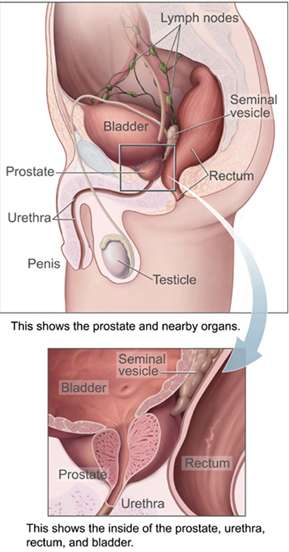

| Prostate | |

Male Anatomy | |

A healthy human male prostate is classically said to be slightly larger than a walnut. The mean weight of the normal prostate in adult males is about 11 grams, usually ranging between 7 and 16 grams.[6] A study stated that prostate volume among patients with negative biopsy is related significantly with weight and height (Body Mass Index), so it is necessary to control for weight.[7] The prostate surrounds the urethra just below the urinary bladder and can be felt during a rectal exam.

Microscopic glands of the prostate Male Anatomy

Male Anatomy The deeper branches of the internal pudendal artery.